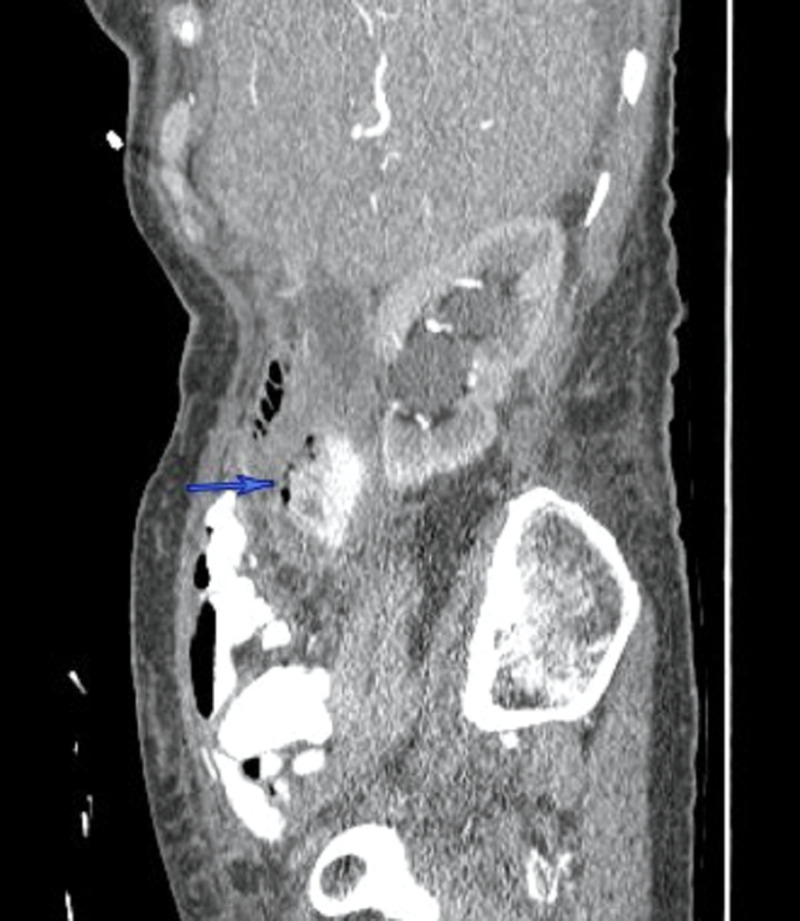

A 77-year-old healthy female presented with right-sided abdominal pain, associated with low-grade fever to 38.2 °C and mild epigastric tenderness. She was hemodynamically stable, with no significant past medical or surgical history. An outpatient CT of the abdomen (Figures 1–2) ordered by her primary care physician (PCP) revealed retroperitoneal fluid collection around the second part of the duodenum, which prompted her to be admitted to the hospital. She was found to have a low-grade fever with leukocytosis, and broad-spectrum antibiotics were immediately started. After a review of the CT images of the abdomen with the interventional radiologist, the retroperitoneal fluid collection was determined to be not amenable to percutaneous drainage. An upper gastrointestinal (GI) and small bowel study showed no evidence of perforation or leak of the stomach or duodenum. Subsequently, an upper endoscopy showed a large periampullary duodenal diverticulum with purulent drainage and normal-looking ampulla. After 72 hours of conservative management with NPO, intravenous (IV) fluid, and antibiotics, the decision was made to proceed with surgery due to persistent epigastric pain and tenderness with an interval increase in the retroperitoneal collection. She underwent excision and primary repair of the diverticulum with a jejunal serosal patch and exploration of the common bile duct (CBD) due to the proximity of the diverticulum to the ampulla. She had an uncomplicated postoperative course and was discharged home on the fourth postoperative day.